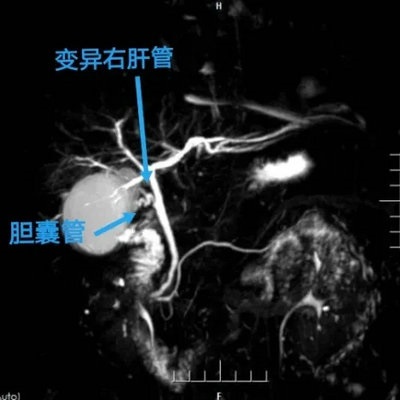

因腹痛病史长,急性加重,此类患者胆道变异率极高,张永主治医师高度重视,立刻为其安排MRCP(磁共振胰胆管造影)检查,发现患者果然存在胆道变异,见胆囊管分出变异右肝管入肝,胆道变异手术风险极高,稍有不慎,就可能发生严重并发症,全面完善术前准备后,张永主治医师为患者安排了腹腔镜微创胆囊切除术,手术如期进行。

术中见患者腹腔内广泛粘连,胆囊体积增大,胆囊壁明显水肿增厚,肝门结构炎性粘连不能明视,在科室主任李晓勇及副主任陈艳军的指导下,张永主治医师术中操作细致娴熟,仔细分离粘连,见胆囊管分出变异右肝管入肝,术中和MRCP预判相同,存在胆道变异。为最大程度规避损伤变异胆管风险,手术从胆囊颈部入路分离胆囊管,顺利切除胆囊,变异胆管无损伤,术中无明显出血,手术十分成功。术后在宋伟华护士长带领的护理团队的精心照顾下,患者恢复良好,很快康复出院,患者及家属对肝胆胰腺外科医护团队无微不至的关怀以及专业果断的诊治水平深表感谢。

▲ 胆道变异图

磁共振胰胆管成像(MRCP)技术,可以将人们正常的胆管走行,胆管的变异情况显示的一清二楚,宛如外科医生手术的“导航图”。有了这张图,医生就会做到胸中有数。规避手术中出现的风险。